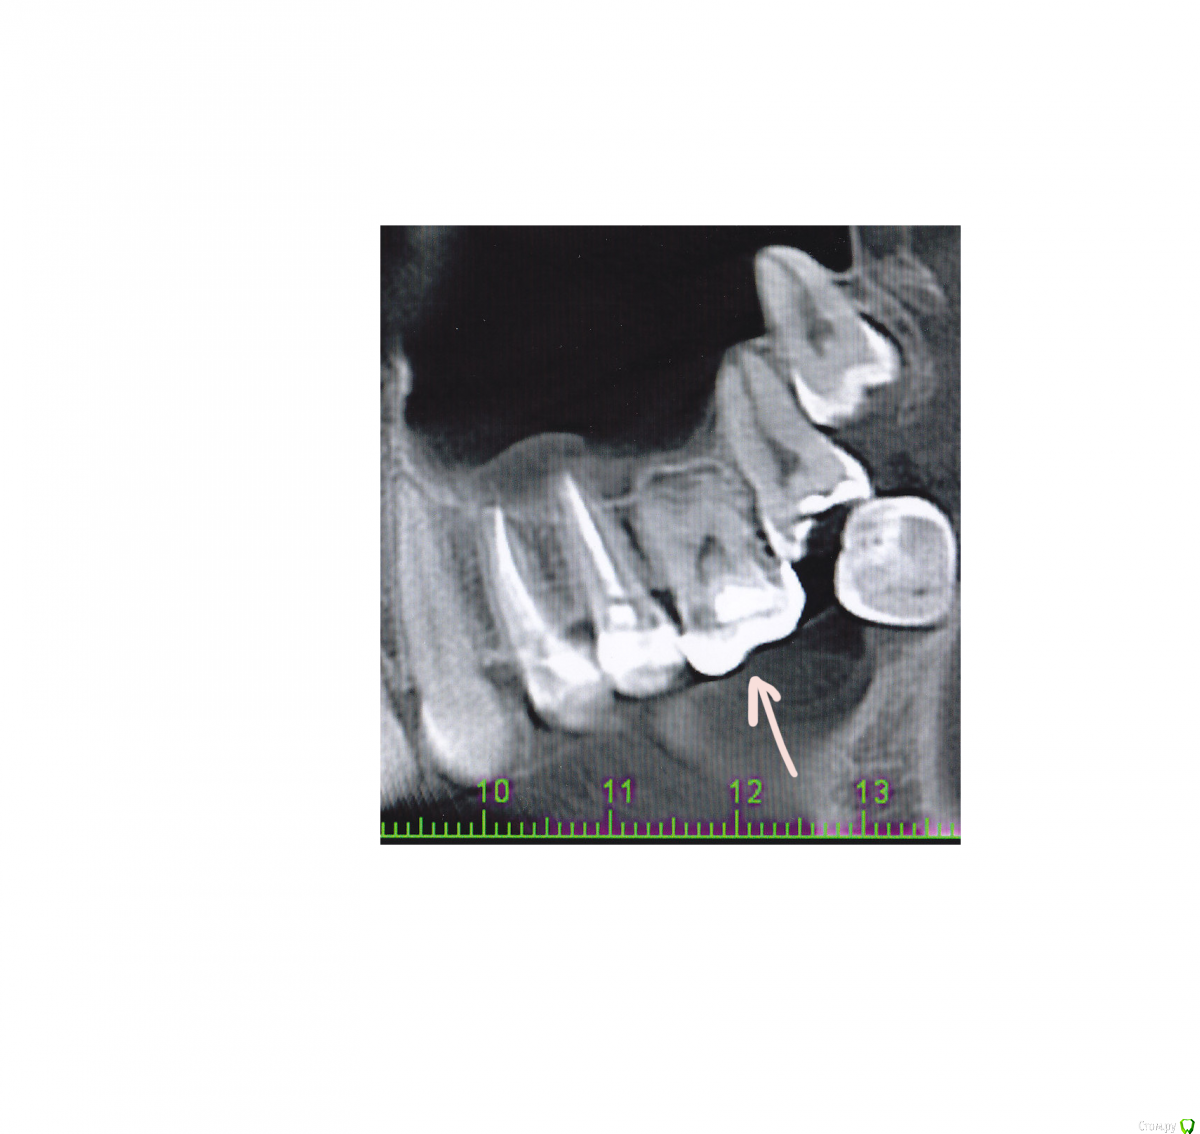

risus Опубликовано 25 февраля, 2015 Поделиться Опубликовано 25 февраля, 2015 (изменено) Здравствуйте!27 лет, пол женЗанялась лечением зубов, перед этим сделали кт, для оценки состояния. Верхнюю 7- ку подлечили, а вот рядом стоящая 6- ка под коронкой.Зуб под коронкой весьма давно, чуть более 10 лет. Сделали ее еще в детской стоматологии, потому что от зуба оставалась одна стенка, на счет наличия или отсутствия нервов не знаю, однако, зуб начинает беспокоить. Кроме того, отсутствует нижняя 6- ка, поэтому верхний начинает «выходить», а под коронку наверняка попадать остатки еды.Доктор говорит примерно следующее, смотря на снимок: «Ничего не ясно, потому что там коронка. Я не могу обещать что, сняв коронку и начав лечить, он будет вылечен в итоге. 50 на 50, его уже не спасти. Возможно, надо будет удалять. Поэтому походи с ним еще года три и удаляй тогда. Тогда- то уж наверняка».Поэтому вопрос: правда ли что по снимку не определить состояние зуба? Врач прав или это просто такой врач, и стоит подыскать другого? Поможет ли прояснить ситуацию, если сделать снимок этого зуба в 3Д?И, уважаемые доктора, могли бы вы прокомментировать состояние 6- ки, если это возможно? Изменено 25 февраля, 2015 пользователем risus Ссылка на комментарий

Scrabble Опубликовано 25 февраля, 2015 Поделиться Опубликовано 25 февраля, 2015 Никакой снимок не даст представления о том, насколько разрушены ткани зуба под коронкой. Если зуб беспокоит, надо снимать коронку-и дальше принимать решение. Можно перелечить-хорошо, нет-значит, удаление и имплантация. А оставлять так, если беспокоит, не надо. Ссылка на комментарий

risus Опубликовано 12 марта, 2015 Автор Поделиться Опубликовано 12 марта, 2015 Никакой снимок не даст представления о том, насколько разрушены ткани зуба под коронкой. Если зуб беспокоит, надо снимать коронку-и дальше принимать решение. Можно перелечить-хорошо, нет-значит, удаление и имплантация. А оставлять так, если беспокоит, не надо.Спасибо за ответ! Все же удалили зуб. Ссылка на комментарий